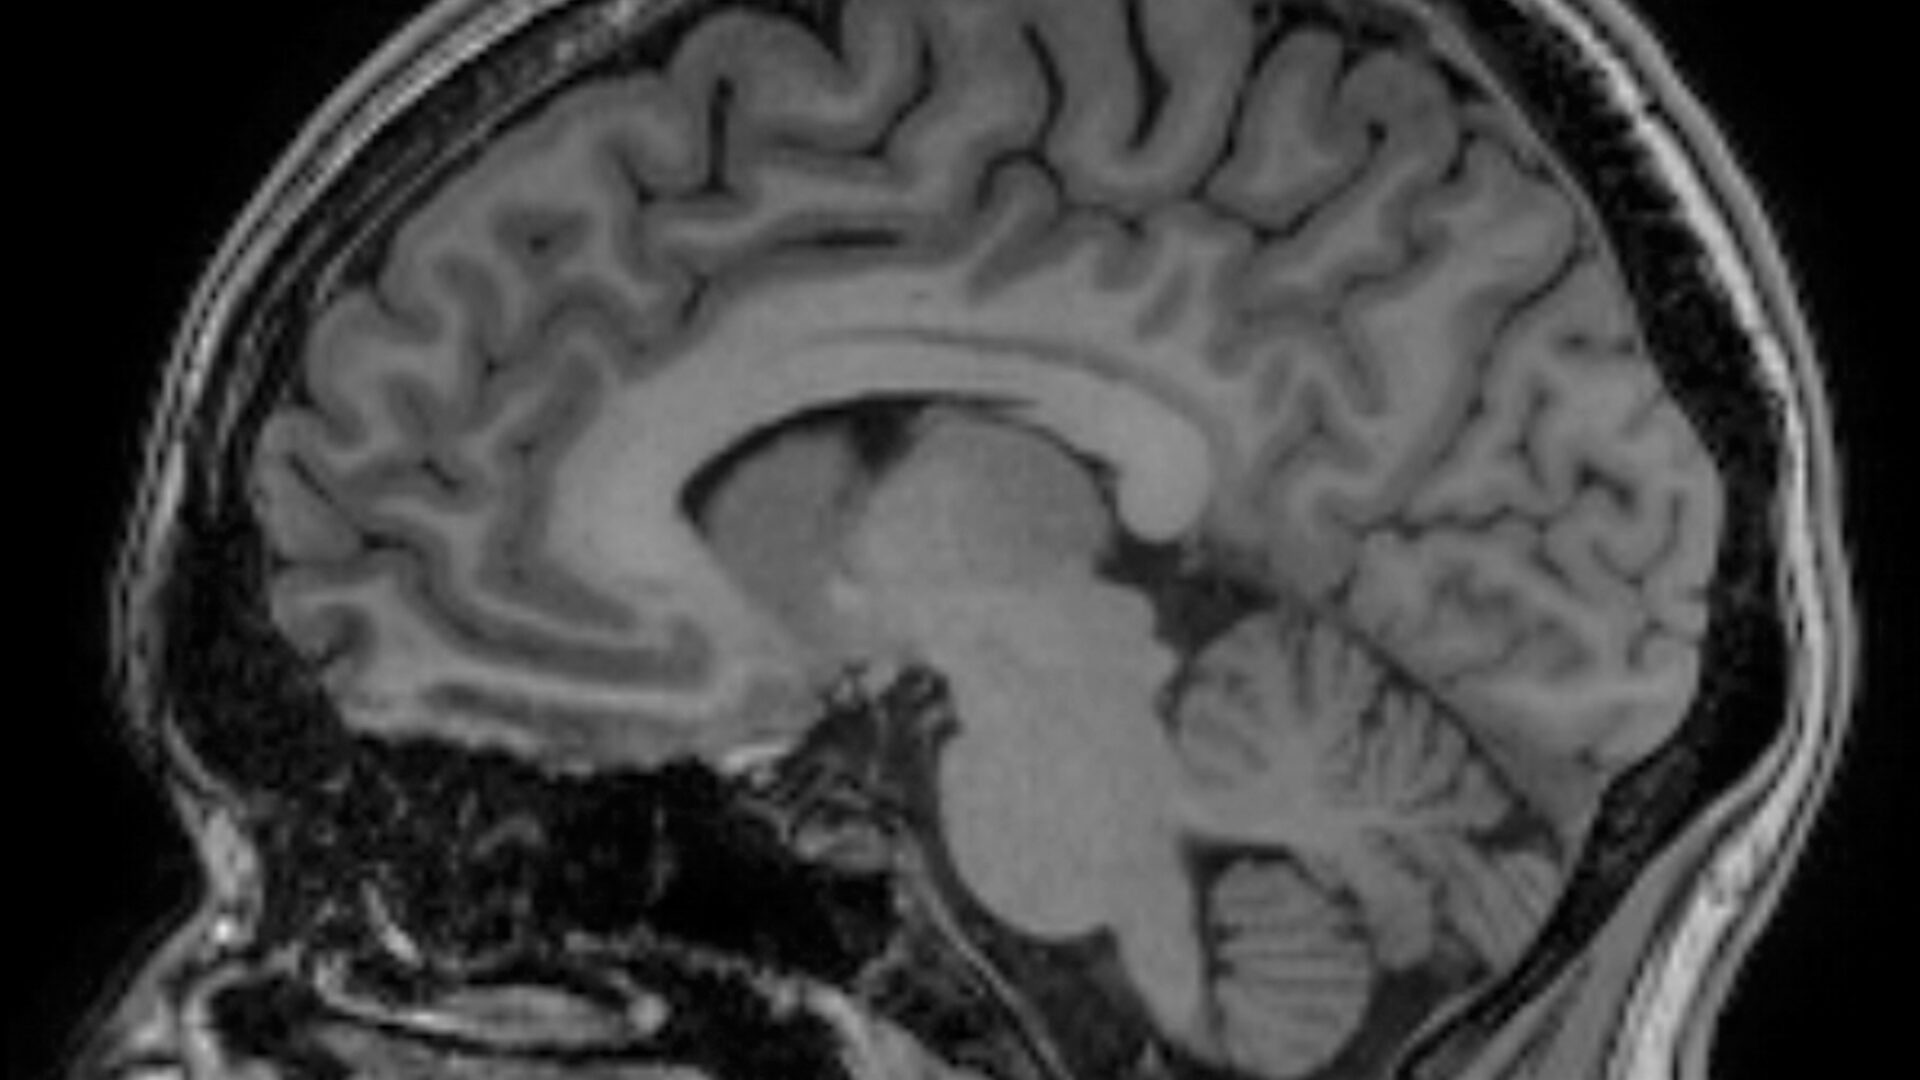

Erasmus MC doet op basis van deze data meerdere studies. Eén daarvan kijkt naar de biologische leeftijd van kinderen. DNA-methylatie verandert in de loop van je leven en kan worden gebruikt om in te schatten hoe oud iemand van binnen is. ‘Soms is iemand biologisch ouder dan zijn echte leeftijd. Maar zien we die snelle veroudering ook terug in de hersenen? Met MRI-scans en deze epigenetische data kunnen we dat uitzoeken.’